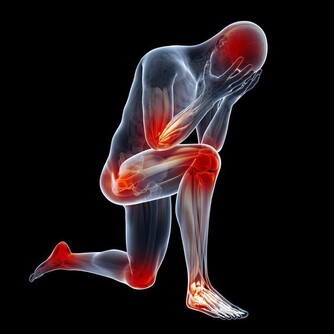

氧化應激會對整個身體的細胞造成傷害,導致衰老和各種疾病,

所以任何時候你都要保護細胞免受氧化應激的損害。

而硒是一種強大的抗氧化劑,飲食中攝入足夠的硒有助於抗衰老。